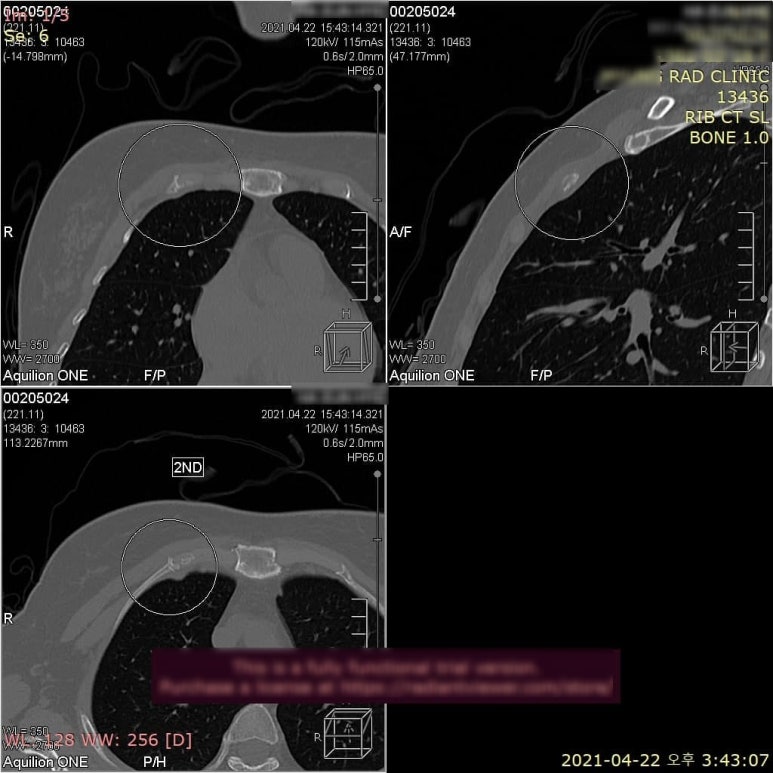

대표적인 것이 갈비뼈, 늑골입니다. 국내외 임상논문에 따르면, 초기 늑골 골절의 50~70%는 엑스레이에서 보이지 않는 것으로 알려져있습니다. 아래 환자분은 부딪힌 뒤로 가슴과 옆구리 통증으로 오신 환자분입니다. 늑골 골절은 엑스레이에서 잘 보이지 않으니 시티 검사가 필요하다고 설명드린 후, 협력병원으로 전원하여 640 시티를 촬영하였습니다.

엑스레이에서 하나도 보이지 않던 골절이 무려 5개나 진단되었습니다.

우측에 제2,3,5,6번 늑골 4군데,

좌측 제10번 늑골까지 총 5개의 다발성 늑골 골절입니다. 늑골 골절은 깁스를 할 수 없어서 통증이 더 오래 갑니다. 심호흡을 하거나 기침만 해도 울리면서 통증이 느껴집니다. 골절된 것도 모르고 담이 결렸다, 근육이 뭉쳤다고 생각해서 열심히 스트레칭 하다보면 골절 부위가 더 벌어집니다.